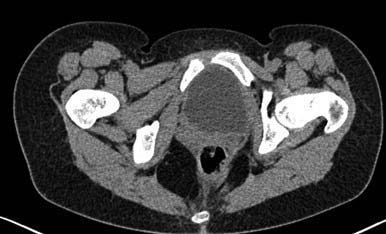

Больная 15 лет. Жалобы: на укорочение правой нижней конечности, хромоту.Анамнез: Со слов болеет с детства, травму отрицает. Ранее за медицинской помощью не обращалась. Последние 2 года отмечает резкое укорочение конечности. Локально: При осмотре отмечается умеренное искривление позвоночника во фронтальной плоскости, умеренная асимметрия лопаток и надплечий. Скошенность таза. Отмечается укорочение правой нижней конечности на 3 см. Движения в тазобедренном и коленном суставах в полном объеме. Нейрососудистых нарушений в периферических отделах нет.

Уважаемый Талгат. Просьба ответить на следующие вопросы: Укорочение у больной анатомическое или функциональное?

Как рентгенологи оценивают состояние крестцово-подвздошных сочленений, не создается ли впечатление о замыкании этого сочленения справа в предшествующие годы, а если это ощущение есть, то что привело к анкилозу этого сочленения. Нет ли по задней поверхности таза в указанной зоне рубца от имевшего место ранее свища?

Наверно целесообразно добавить,что болевого синдрома нет,движения в суставе в полном объёме.Я бы уточнил,что жалобы скорее косметического характера(асимметрия при ходьбе и западение вертельной области справа. Укорочение фигурировало как единственный диагноз в направлении на лечение к нам.Компенсация "укорочения" увеличением высоты каблука обуви не устраняет асимметрию таза и в статике и мало улучшает походку.Вопрос-стоит ли в конкретном случае идти на тройную остеотомию таза и латерализацию вертлужной впадины? Мне представляется,что не стоит.